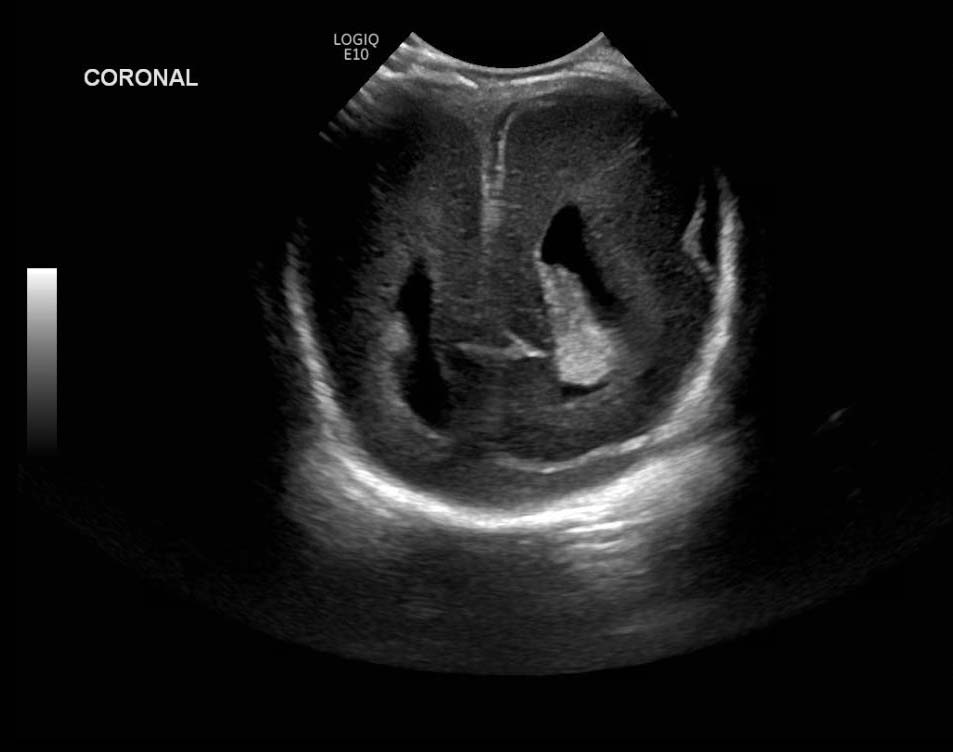

Age: 4 days (born at 24 weeks)

Sex: Male

Indication: Evaluate for germinal matrix hemorrhage

Grade 2 germinal matrix hemorrhage

Sample ReportLeft germinal matrix hemorrhage involving the caudothalamic groove and layering in the occipital horn of the left lateral ventricle without hydrocephalus (grade 2).

No abnormal brain parenchymal echogenicity or extra-axial collections.

Premature sulcation pattern.